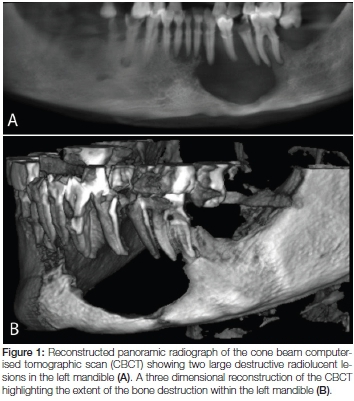

Imaging: Uncovering Hidden Lesions

Imaging studies, such as computed tomography (CT) and magnetic resonance imaging (MRI), are essential when a patient presents with an unusual presentation of jaw pain. In the reported case, a CT scan of the neck revealed a large soft tissue mass with associated bony destruction in the mandibular region. Such images are invaluable in providing a roadmap for further investigative measures. However, in about 5% of cases, these scans may not show any abnormalities, which makes the diagnostic process all the more overwhelming and complicated.

When the initial clinical presentation is ambiguous, advanced imaging modalities such as CT scans and MRI are deployed to dig into the deeper aspects of the lesion. For example, the CT scan in the discussed case revealed not only a mass in the mandible but also signs of bony destruction, which immediately raised red flags about its malignant potential.